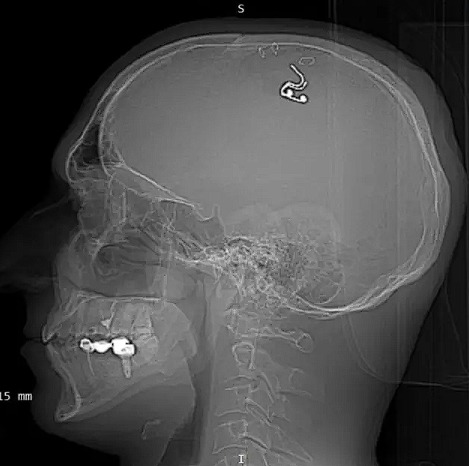

Matkapla kafatasını delen adam beynine çip yerleştirdiğini iddia ediyor. Raduga'nın ameliyatı bir apartman dairesinde gerçekleştirdiği bildirildi.

Raduga yaptığı açıklamada 1 litreden fazla kan kaybı yaşadığını ve neredeyse öleceğini söylerken yaptığı ameliyatın sonuçları için "gelecekteki rüya kontrol teknolojileri için harika umutlar" doğuracağını iddia etti.